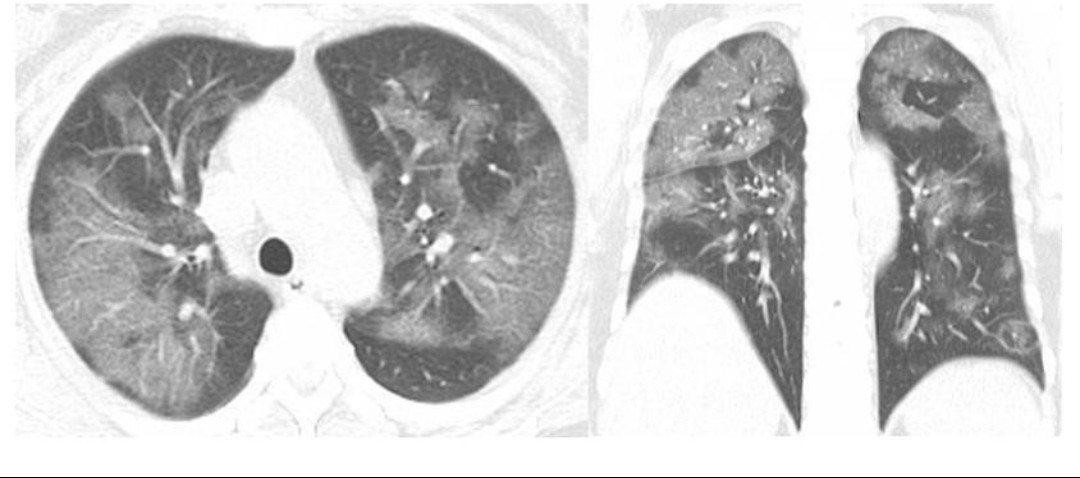

Медицинская тема: легочные осложнения при пневмонии